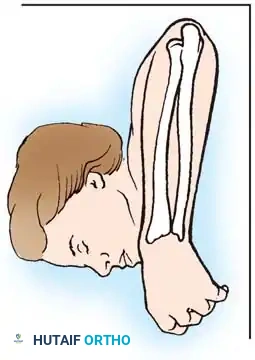

In cases of severe instability or concomitant ECU subsheath disruption, open capsular repair and ECU stabilization are required.

Open repair of the dorsal capsule and TFCC, ensuring robust closure and stabilization of the ulnar-sided structures.

Stabilization of the ECU tendon and subsheath, a critical step in addressing complex ulnar-sided wrist trauma.

If the DRUJ remains unstable after soft tissue repair, temporary transarticular K-wire fixation may be necessary to protect the repair during the initial healing phase.

Radiographic confirmation of temporary transarticular K-wire fixation stabilizing the DRUJ following complex TFCC repair.